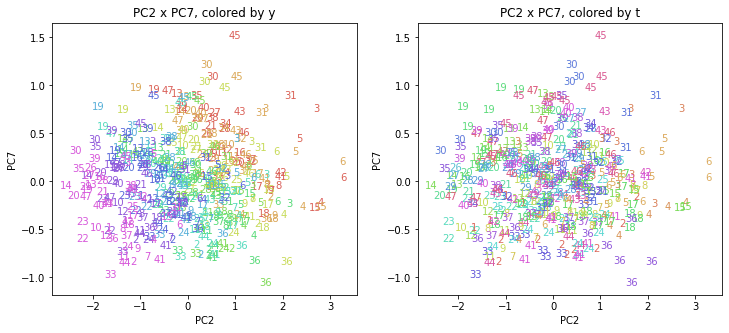

PCAの結果の第n主成分をPCnと表記します。

医療費データの場合と同様に、PCAの結果を見やすく表示するため、seabornのカラーパレットを使って、年月別、都道府県別に色分けして図示してみます(左側が年月別に色分け、右側が都道府県別に色分け)。PC1~PC8まで表示しました。

都道府県番号の表示

上の色分けだけでは都道府県が区別しにくいので、医療費データの場合と同様に、点の代わりに都道府県番号をプロットした図も描いておきます(色分けは上と同じ)。

医療費データの場合ほどはっきりとはしていませんが、PC2が概ね時間の経過を表す成分で、残りの成分が時点によって変わらない地域の特徴を表す成分となっているようです。

また、PC1×PC3を見ると、47沖縄が他の都道府県からかなり離れたところに位置しており、沖縄の地域差が際立っているのが分かります。これは、以前別の記事で年齢階級のない健診データでPCAを実行した場合と似た結果となっています。

今回は、医療費データと同様に、健診データ240次元についてPCAを実行してみました。PCAの結果、医療費データの場合ほどはっきりしとはしていませんが、第2主成分が概ね時間の経過を表す成分で、時間軸に沿った全体的な動き(全国的な動き)を表しており、それ以外の成分が地域の特徴を表す成分で、この10年間あまり変わっていないことがわかりました。